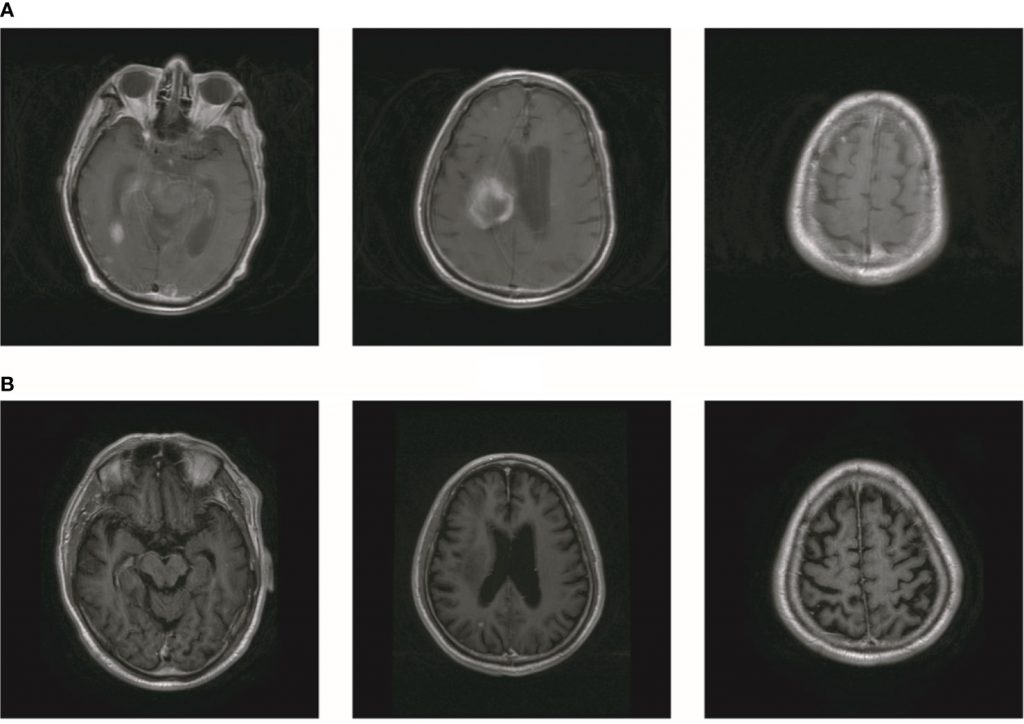

2019年10月,患者出现头晕、右髋疼痛。PET显示右侧髂骨和右侧坐骨多发骨转移(图2A)。此外,大脑中有多个转移灶(图2A)。对比增强磁共振成像(MRI)揭示了九个BM(图2B)。实验室分析显示CEA水平为3.6。我们建议对右侧髂骨进行活检。由于患者颅内压高,头晕加重,他和家人拒绝活检。在通过NGS检查的血液样本中未检测到ALKr 。继刘的报告,患者接受了针对转移灶的全脑放疗(WBRT)联合同步综合强化(SIB)。WBRT的剂量为39.6Gy,分22次给药,SIB的剂量为55Gy,分22次给药(图2C)。患者还接受了右侧髂骨病变的放射治疗(60Gy,24个疗程,图2D)。尽管放疗使患者的右侧髋部疼痛有所改善,但他的颅内压却恶化了。该患者在完成10次颅内放疗后接受了MRI。MRI显示BM的数量增加到大约50(图3A)。经过慎重考虑,我们决定完成WBRT。完成WBRT后,患者昏迷,MRI显示大约80个BM,包括脑干中的一些(图3B)。据报道,根据组织学和配对液基细胞学标本之间的免疫染色,ALK状态的总体一致率为100%。然而,孤立性中枢神经系统(CNS)进展患者的基因组改变检出率较低。由于血液检测结果值得怀疑,患者每天两次接受艾乐替尼Alecensa(Alectinib)600mg。口服艾乐替尼Alecensa(Alectinib)一周后,患者意识逐渐恢复,一个月后身体症状也逐渐好转。MRI显示BM数量减少至约60个,转移肿瘤总体积减少(图4A))。一些转移灶消失了,尤其是在脑干中。然而,由于患者自主终止降压治疗,右侧丘脑出血并破裂入脑室,导致脑出血。患者因脑出血接受治疗。同时,患者继续服用艾乐替尼Alecensa(Alectinib)。出现出血后经过一个月的治疗,患者的病情逐渐稳定。MRI显示大部分血肿被吸收,BMs数量进一步减少至约20个(图4B)。总转移性肿瘤体积也进一步减少。

图4

图4艾乐替尼Alecensa(Alectinib)治疗后BM数量减少。(A) MR显示脑转移数目减少至约60。(B)脑转移数目进一步减少至约20。